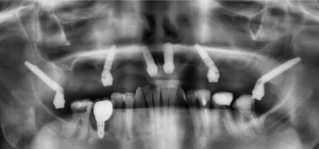

Ход лечения:

Мы провели тотальную имплантацию верхней челюсти с применением птеригоидных имплантов. Эта методика позволяет надежно зафиксировать импланты в плотных отделах крыловидной кости, обходя зоны выраженной атрофии и избегая объемных костнопластических операций. Были удалены несостоятельные зубы и старые ортопедические конструкции, после чего установлены импланты по протоколу тотальной реабилитации, включая птеригоидные импланты в дистальных отделах.